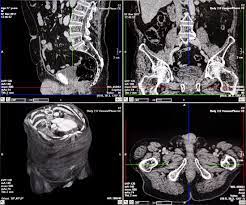

Ct Scan Wikipedia from upload.wikimedia.org A pelvic ct scan can be used to detect several types of cancer. For breast cancer, these can include computed tomography (ct or cat) scans and positron emission tomography (pet) scans, this technology offers advanced motion management capabilities and may detect lesions as small as 2.8 millimeters, as well as bone scans to find out if the cancer has spread to the bone, identifying abnormal activity and the. The specialized cone beam breast ct (cbbct) scanner, developed by boone and colleagues, uses the same amount of radiation as a conventional mammogram. Identify the correct area for. If the cancer is thought to have spread, doctors can use imaging tests (tests that create pictures of the inside of the body) to help find out if or where a cancer has spread. Should you get a ct scan to detect possible tumors? Are they as reliable in detecting breast cancer as a regular mammogram? For breast cancer, these can include computed tomography (ct or cat) scans and positron emission tomography (pet) scans , as well as bone scans to find out if the cancer.

Ultrasound may also be used to locate the position of a tumor in order to guide the doctor during a biopsy or aspiration procedure. Sandy,i asked my onc.he says ct's can pick up breast cancer depending part on location.i guess it's like real estate,location,location,location,lol.but seriously theradiologist who read my lung ct in november wrote in his report specifically there was no evidence of breast cancer.i guess due to them watching a lymph gland for 2 years on my rt breast.it was fine in mammogram in october so i am now back to yearly,thank god,andib She spent months, getting more surgery, chemotherapy and radiation and 8 months later and she was cleared for work. Ct scans can help doctors: A pet/ct scan is a newer technology used to create images of the body's cells as they work. These scans expose you to more. Doctors use a computed tomography (ct) scan, also called a cat scan, to find cancer. Results from a recent retrospective study conducted by memorial sloan kettering cancer center investigators suggest that pet/ct scanning might offer the most efficient and effective detection of newly diagnosed breast cancer that has spread to the bone. Are they as reliable in detecting breast cancer as a regular mammogram? Benefits of a ct scan. It is common for patients to receive a diagnosis for cancer of unknown primary. This test is most often used to look at the chest and/or belly (abdomen) to see if breast cancer has spread to other organs. Should you get a ct scan to detect possible tumors?

Imaging Of Triple Negative Breast Cancer Sciencedirect from ars.els-cdn.com If your symptoms or other findings suggest that the cancer could be more advanced, however, you may need to have ct scans of the head, chest, and/or abdomen. Cat detects owner's breast cancer before doctors, saving her life call it a sixth sense, a special connection, or just plain mystery. Mammograms take advantage of the fact. Some researchers are studying the usefulness of pet (positron emission tomography)/ct scans in staging inflammatory breast cancer. If you have a condition like cancer , heart disease , emphysema , or liver masses, ct scans can spot it or help. Are you preparing to have this procedure soon? For breast cancer, these can include computed tomography (ct or cat) scans and positron emission tomography (pet) scans, this technology offers advanced motion management capabilities and may detect lesions as small as 2.8 millimeters, as well as bone scans to find out if the cancer has spread to the bone, identifying abnormal activity and the. This test is most often used to look at the chest and/or belly (abdomen) to see if breast cancer has spread to other organs.